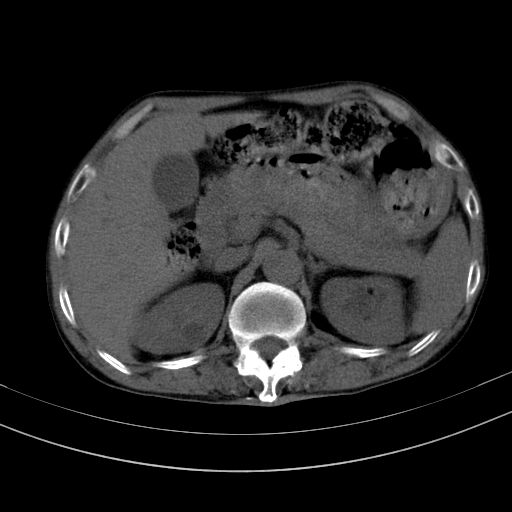

以下是引用dyqct在2010-1-9 17:56:00的发言:[br]考虑:1.双肾囊肿,左肾积水结石、旋转不良。[br] 2.右侧腹直肌血肿或纤维瘤。[br]肠道准备不好。做个增强。